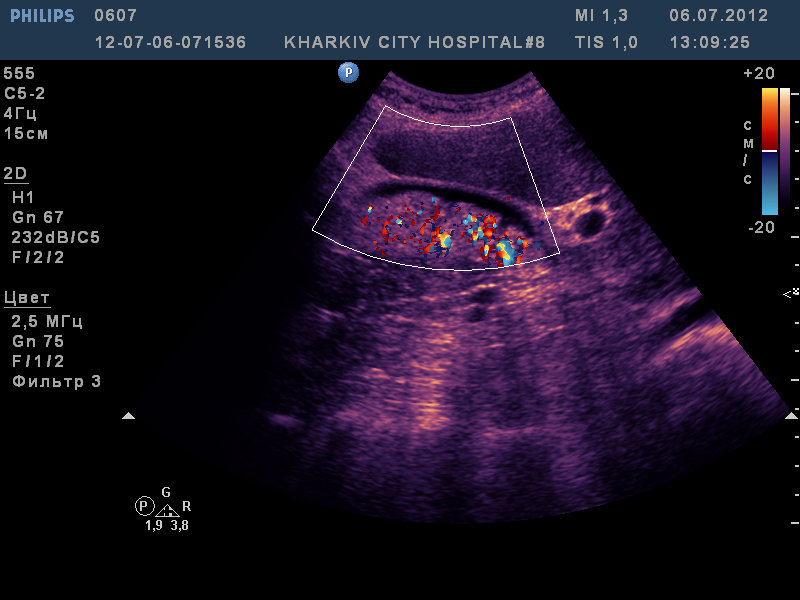

Данную картину расценил на первый взгляд как сладж. На автомате включил сосудистый режим и изменил свое мнение. Решил что вероятно вижу папиллярную аденокарциному.

В залючении отписался : "...Внутри полость выполнена неоднородным повышенной эхогенности образованием с наличием участков кальцификации и выраженным сосудистым рисунком.

Заключение: образование желчного пузыря. Рекомендовано КТ, консультация хирурга!"

Насколько я понял, Ваше заключение об опухоли в бОльшей степени базируется на данных ЦДК. Получив такую картину дальше нужно было получить поток с помощью импульсной доплерографии и убедиться в его воспроизводимости. Твинклинг-артефакт дает специфический сигнал при импульсной доплерографии, его сложно с чем-то спутать.

На опухоль желчного пузыря не очень похоже, они обычно более низкой эхогенности, и конечно в них не бывает такой богатой васкуляризации. Это вероятнее всеже ЦДК артефакты.

пересматривал пациентку. К сожалению протормозил с видео и не записал. То что я расценил как сосудистый рисунок, а вы как артефакт мерцания как было так и есть. Изменилась стенка ж.п.- утолщилась и стала какой то неоднородной . У пациентки стал низкий гемоглобин и СОЭ 46